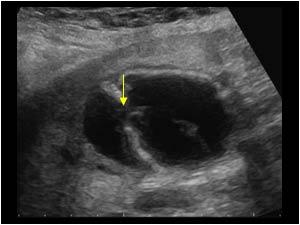

Mirizzi SYndrome

impacted stone in the cystic duct or GB neck

presence of two tubular structures representing the bile duct above the level of the cystic duct

Mirizzi SYndrome

impacted stone in the cystic duct or GB neck

presence of two tubular structures representing the bile duct above the level of the cystic duct